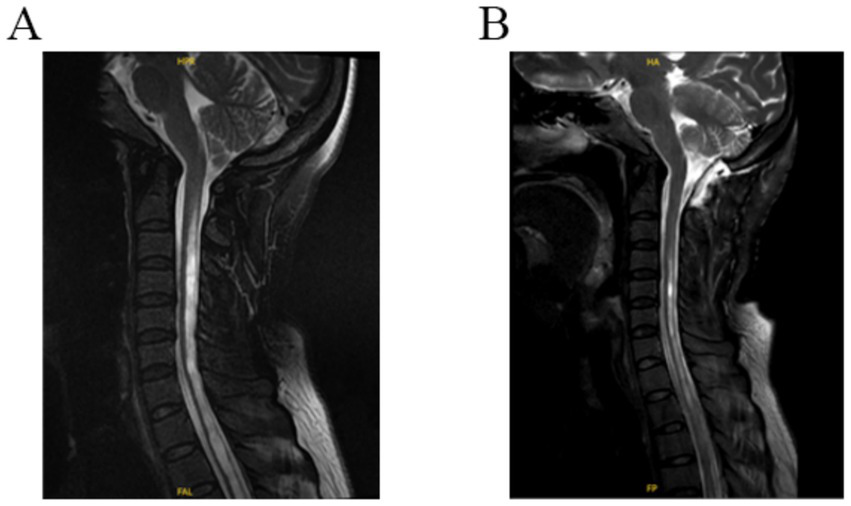

2.4 Follow-up and evaluation of surgical outcomes

All patients were followed up for 6 to 33 months, and the symptoms and signs before and after surgery were compared. Six months after surgery, the outcome was evaluated according to the Chicago Chiari outcome scale (CCOS) scores: 13–16 were improved group; 9–12 were unchanged group, and 4–8 was worse group (12, 13). Changes in syringomyelia were observed on MRI of the cervical spine, which was more than 50% smaller than that before surgery and were judged to be improved (Figure 2). Postoperative complications such as fever, incision and intracranial infection and cerebrospinal fluid leakage were observed.

Figure 2

(A) Preoperative T2 MR-weighted images showing cerebellar tonsils through the foramen magnum and syringomyelia. (B) Postoperative T2 MR-weighted 3-day image revealing a decrease in the size of syringomyelia and an enlargement of the subarachnoid space of the foramen magnum.